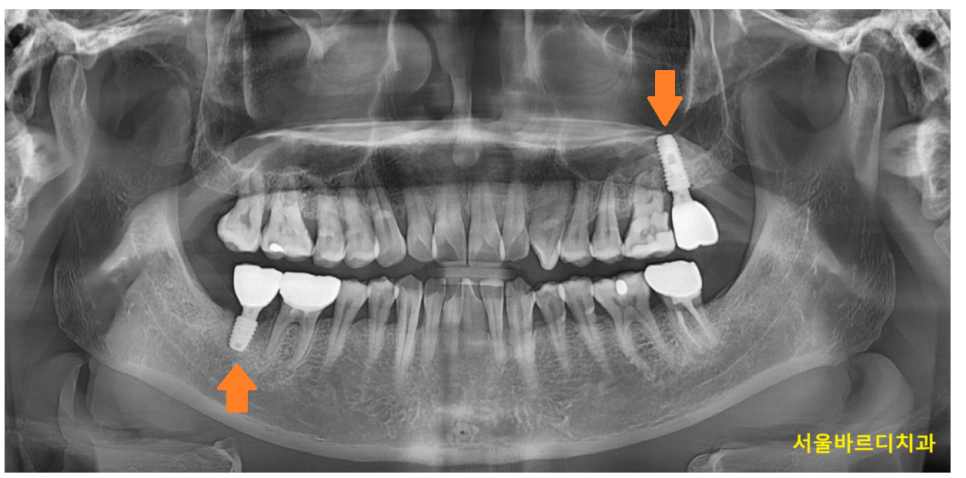

250403 수술 완성 모습